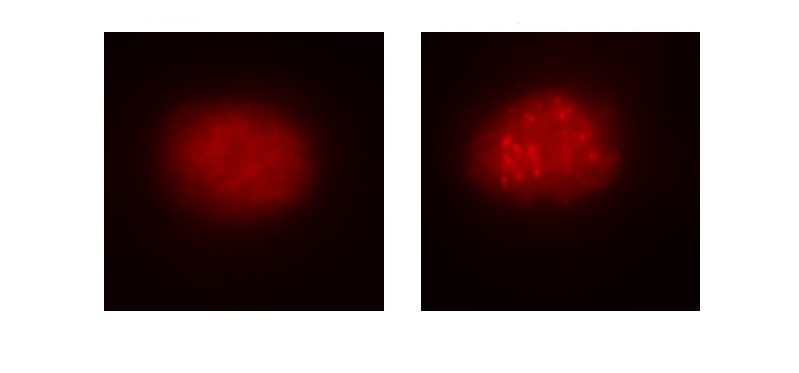

Un estudio propone IRAK4 como una nueva diana terapéutica en la leucemia linfática crónica